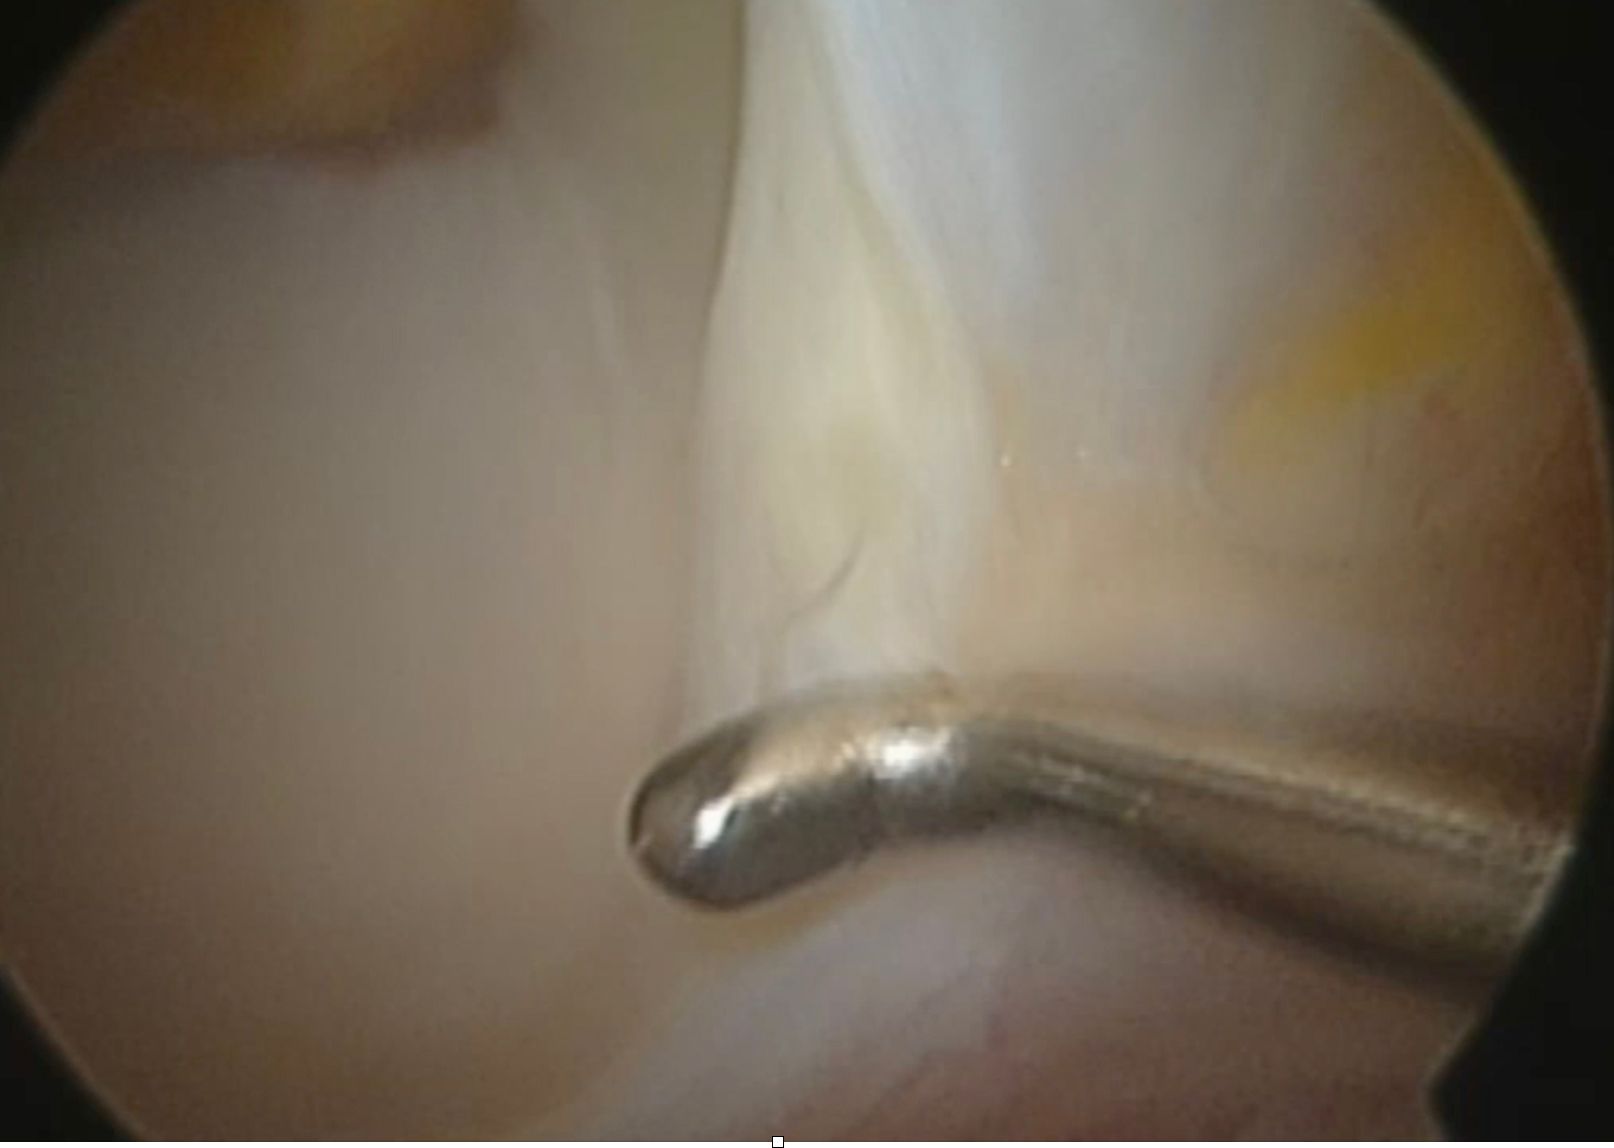

The second stage involves a comprehensive assessment of all joint damage, then repairing or reconstructing the labrum. As we have seen, the labrum accounts for around 20% of joint stability and is also a highly innervated region. It is essential to check the condition of the cartilage. Apart from subchondral bone drilling (as described by Pridie) or microfracturing (35) there is no truly effective solution for damage to the acetabular cartilage. Small isolated lesions on the head of femur do however respond very well to the mosaicplasty technique (36). Very often there is an anterior lateral band of chondromalacia causing the snap described by so many patients (Fig. 20). Unfortunately, not much can be done with this cartilage, but repairing the labrum and reducing the instability will almost always solve the problem. If the labrum cannot be repaired, it can be attached to the acetabular wall following a minor acetabuloplasty. Some authors suggest reconstruction using either a band of fascia lata, a hamstring tendon or an allograft (37). The femoral head should be inspected, and you will often find a small cam or lack of offset. A burr should then be used to recreate the offset. In case of a pincer impingement gentle trimming of the acetabular rim might be indicated. Always check for any impingement in flexion, internal rotation and external rotation. The ligamentum teres is easy to examine. Simply place the joint in external rotation. It can be removed if necessary, although some authors suggest reconstruction (38).

The third stage is the capsule plasty (7, 39, 40) designed to restore tension to the capsule as with a Bankart shoulder repair (Fig. 21). Several techniques have been described, and there is no doubt that it works relatively well for instabilities where the bone is only a minor contributing factor. Patients are ordered to avoid full weight bearing for a month, and especially to avoid excessive extension of the hip. Personally, I make them wear a wedge insole for the operated leg for 35 days to encourage recovery. With these hips, it makes no sense not to repair the capsule, due to reports of recurring postoperative dislocations after arthroscopy (41, 42).